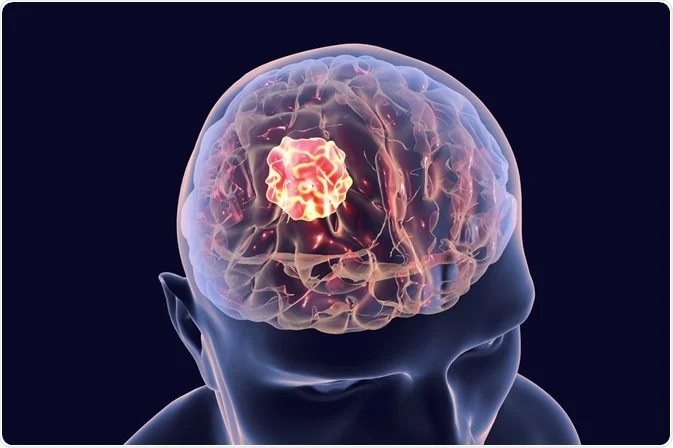

Brain Tumor

A brain tumor is a Enhancement of abnormal cells that have formed in the brain. Some brain tumors are cancerous (fatal), while others a...